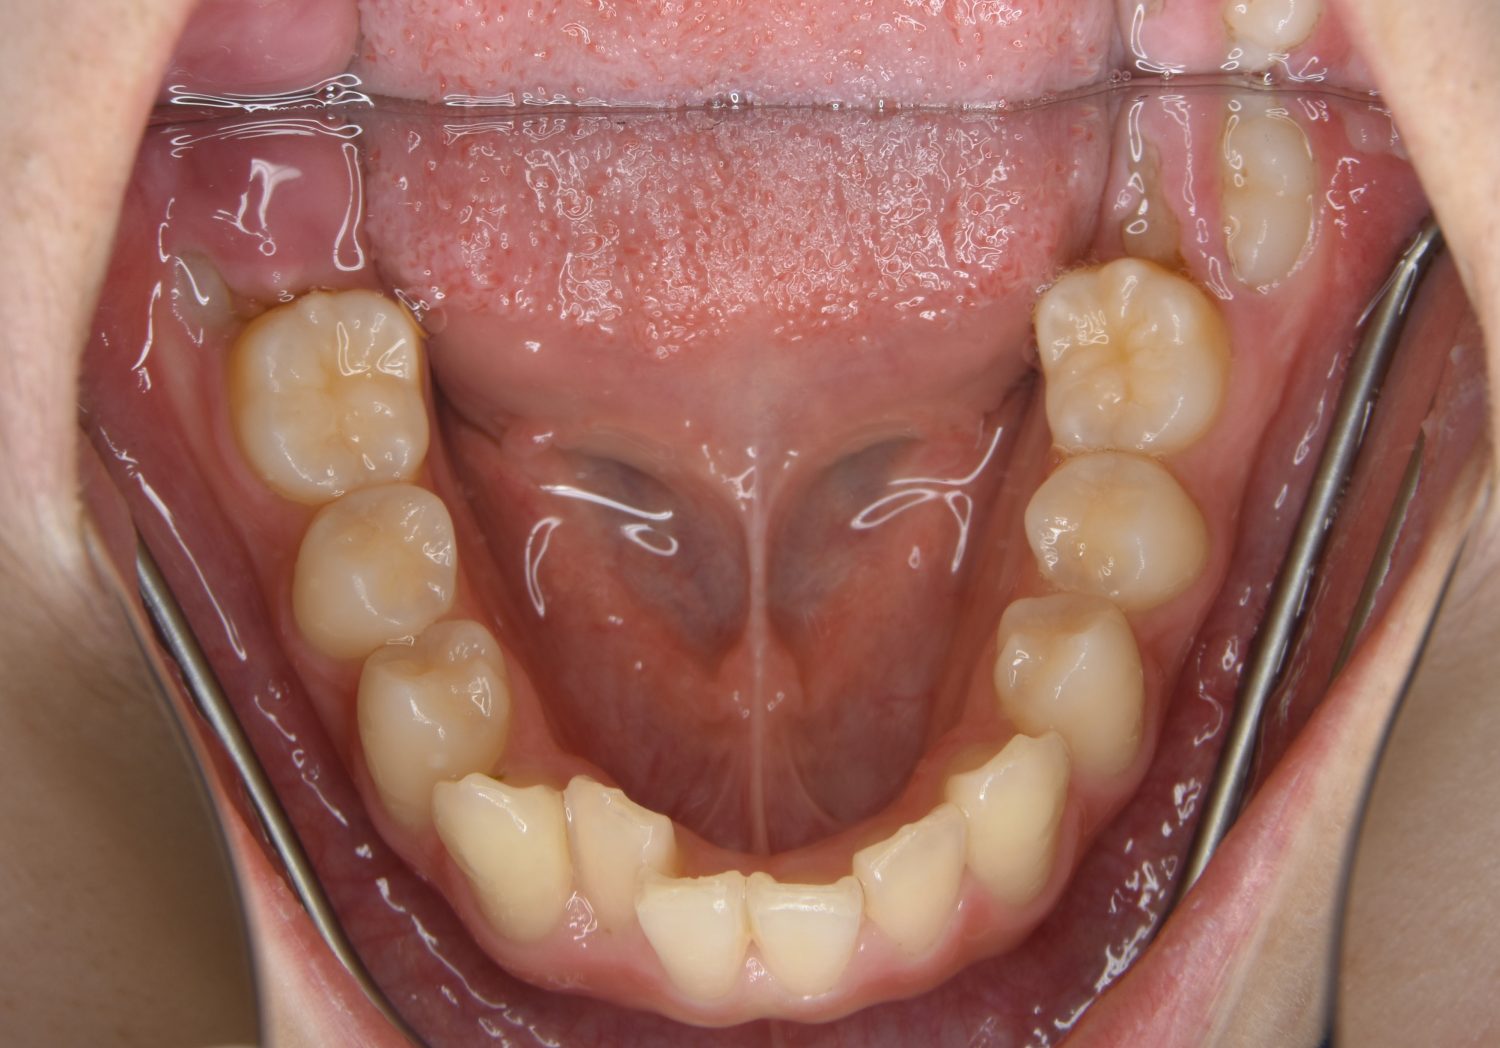

叢生の症例紹介②

Before

After

主訴

歯の凸凹を治したい。

治療内容

アライナー(インビザライン)にて非抜歯で治療を行いました。

上下前歯部に叢生(凸凹)が認められる状態でした。歯列の遠心移動を行うことで機能面および審美面が改善されました。